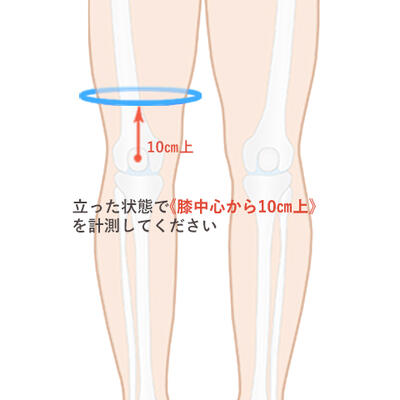

楽天市場】【内側半月板】《固定用》膝サポーター|エクスエイド。楽天市場】【内側半月板】《固定用》膝サポーター|エクスエイド。膝サポーター 膝 サポーター 医療用 医療 スポーツ 内側半月板。米10キロ 天のつぶ 雪若丸(各5キロ×1袋)。内側半月板損傷|おすすめの膝サポーター。半月板損傷 |SPORTS MEDICINE LIBRARY|ザムスト(ZAMST)。内側半月板損傷におすすめの膝サポーター集 コルセットミュージアム。半月板損傷 |SPORTS MEDICINE LIBRARY|ザムスト(ZAMST)。半月板損傷(断裂)meniscus-injury(rupture)について | ゆうき。右膝内側半月板損傷 前野整形外科 - 【公式】esaote 日本で唯一。外側半月板損傷|おすすめの膝サポーター。エクスエイドニー 固定用内側半月板損傷用 右膝用です。半月板損傷 – McDavid|サポータ-ブランドのマクダビッド。※外側半月板損傷 左膝膝としても使えます定価16980円でした。1度着用いたしました。円板状半月板損傷を治す!>膝サポーターのメソッド。固定力がとてもあり、安定してます。サイズM